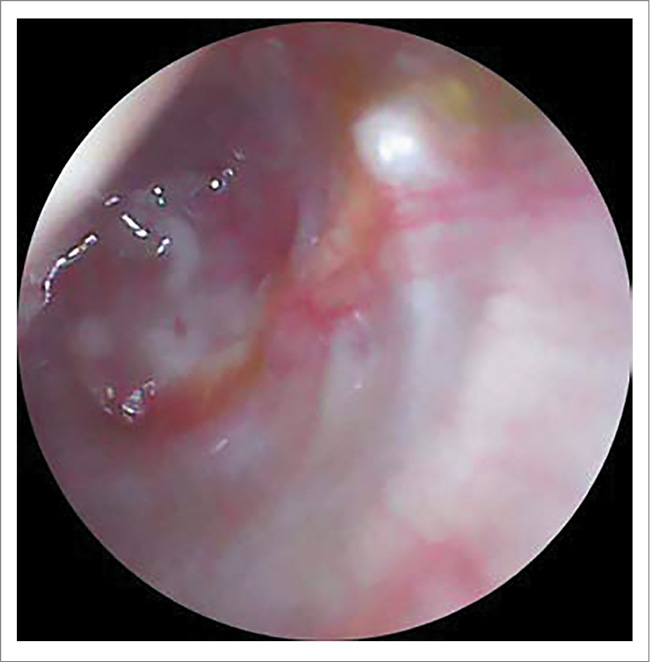

ЛОР-статус на момент поступления: AD – околоушная, заушная область не изменена, при пальпации безболезненна. При отоскопии: наружный слуховой проход несколько сужен из-за отечности стенок, в просвете визуализируется скудное гнойное отделяемое. Определяется тотальная перфорация БП, слизистая медиальной стенки барабанной полости утолщена, покрыта серо-белым субстратом (фибрин? некротические ткани?); рис. 1.

Рис. 1. Отоскопическая картина справа при поступлении: тотальная перфорация БП, слизистая медиальной стенки барабанной полости утолщена, покрыта серо-белым субстратом (фибрин? некротические ткани?).